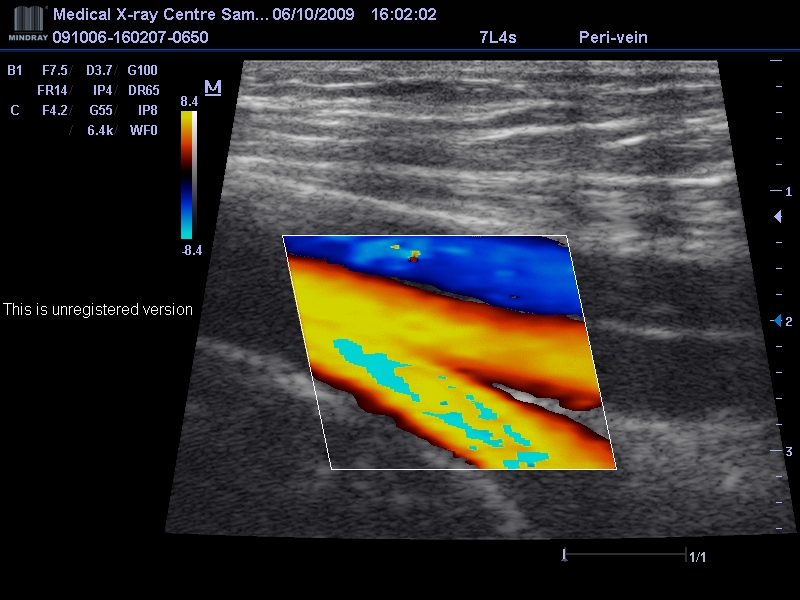

Многопрофильное частное лечебно - диагностическое учреждение. Все виды диагностики ( УЗИ, КТ, МРТ ) Консультации узких специалистов любого профиля. На базе центра работает лечебно - диагностический кабинет флеболога ( весь спектр флебологических услуг)Консультация флеболога, УЗИ вен Приём ведёт хирург – флеболог Красильников Андрей Викторович. На консультации проводится дуплексное сканирование вен, которое сочетает в себе допплерографию и режим сканирования в реальном времени. При обнаружении первых симптомов заболевания как можно скорее обратитесь к флебологу, который поставит диагноз и порекомендует лучший способ лечения или профилактические и поддерживающие меры (лечебный трикотаж, медикаментозную терапию, физиотерапию, лечебную физкультуру).Существует три основных направления в лечении варикозного расширения – склерозирование (введение в вену специального вещества, после чего она склеивается и постепенно исчезает), ЭВЛК (лазерная коагуляция) и хирургический метод. запись на приём по тел.(846)373-30-30, 373-30-33, 990-89-58 информация на сайте САМАРСКИЙ ФЛЕБОЛОГ доктора Красильникова http://phlebologsamara.ru/